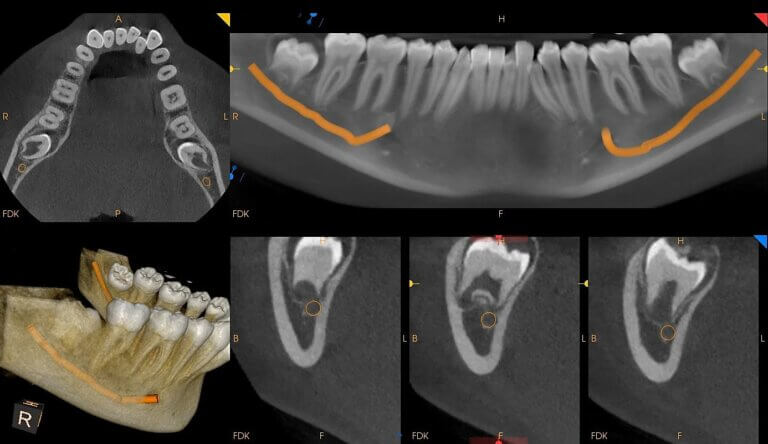

CBCT (3D Dental Imaging)

Cone Beam CT (CBCT) provides detailed 3D imaging of teeth, bones, and soft tissues. Essential for accurate diagnosis and treatment planning. Commonly used in implant planning, orthodontics, and oral surgery. Safe and quick scan with minimal radiation. Enhances precision and outcomes.